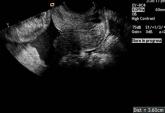

NewsCervical Length Screening to Reduce Preterm Birth Author:Dr. Meena KhandelwalPublish date: October 3, 2012 Read More